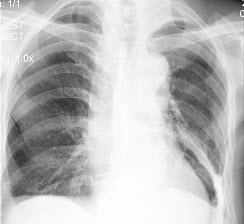

73、单项选择题

患者输液过程中突发胸闷、气急、咳痰,胸片如图,最可能的诊断为()

A.矽肺合并感染

B.中央型肺水肿

C.真菌感染

D.间质性肺水肿

E.腺病毒肺炎